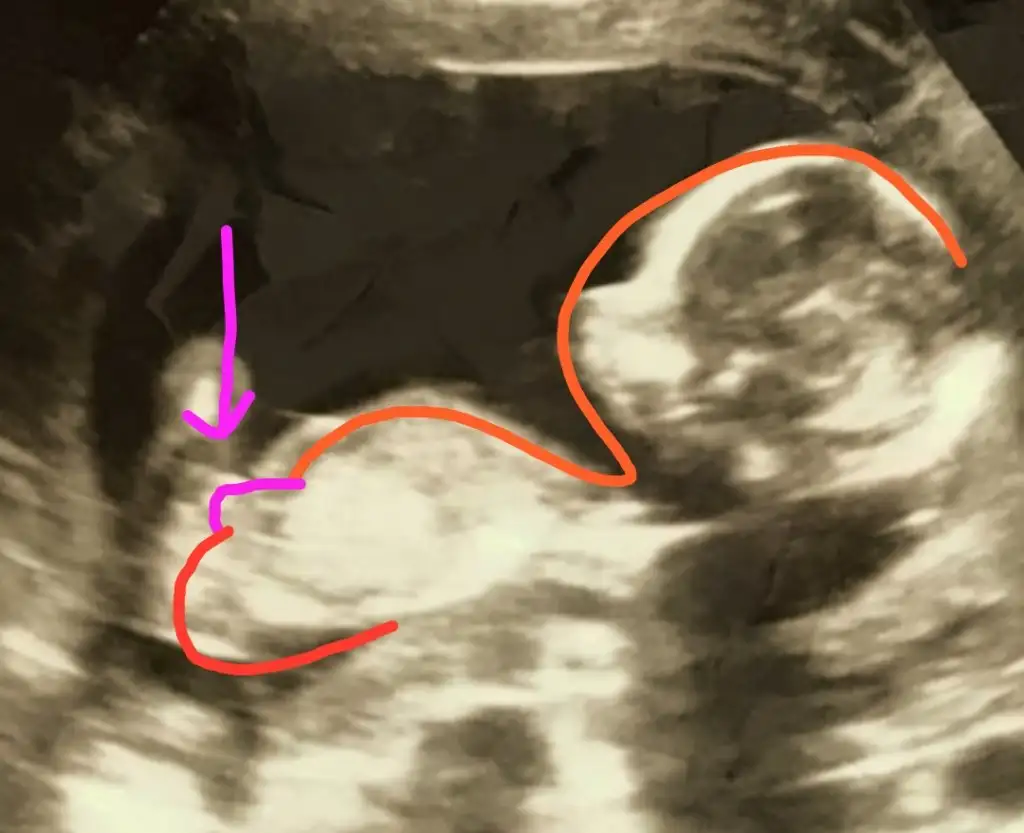

Evet erkek bu bebek Allah sağlıkla kucağınıza almayı nasip etsinMerhaba 11+4 te kız demişti doktor ama dün gittiğimiz kontrolde Erkek dedi .

Slm canım ben bugün rekle oynadım ve buna %80 kız görünüyorMerhaba 11+4 te kız demişti doktor ama dün gittiğimiz kontrolde Erkek dedi .

Canım bacak arasında bişey varSlm canım ben bugün rekle oynadım ve buna %80 kız görünüyoryani bacak arası dolu olsa muhakkak birşeyler görünürdü gerçi kordon vs dedin ama ne bilim kafa desen tıp desen kız gibi Eki Görüntüle 2748938

doktor erkek dedi ama önden inceleyemedi kordon kapatıyorduyani ben kurcalamasam erkek deyip gönderecekti ben çok ısrar edince tekrar çağırdı ay hadi inşalah yarın gidiyorum söylerim pipiyi yemiş mi duruyor mu

Şimdi doktordan çıktık nubu kız olan evladımız erkek